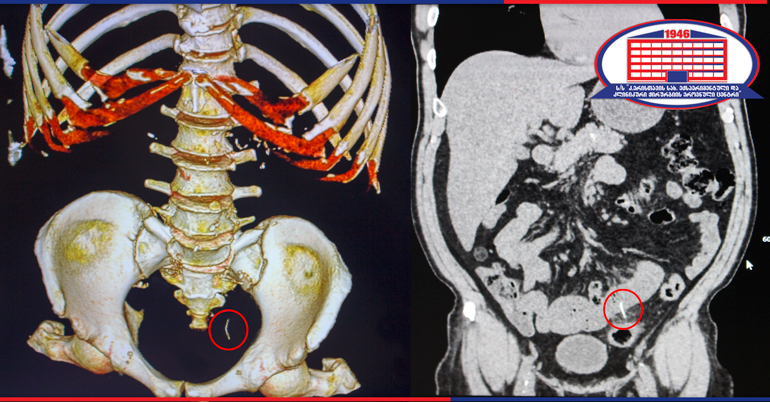

კლინიკის რადიოლოგმა ირაკლი გიგიაძემ შენიშნა, რომ წვრილი ნაწლავი უცხო სხეულით იყო დაზიანებული. დაუდგენელი სახეობის უცხო სხეული ნაწლავის სანათურიდან მუცლის ღრუში გამოდიოდა. პაციენტს ჩაუტარდა ლაპარასკოპია. მოიძებნა და ამოღებულ იქნა უცხო სხეული, ხოლო წვრილი ნაწლავის დაზიანებული უბანი გაიკერა.

უცხო სხეული, რომელიც ქირურგებმა პაციენტის წვრილი ნაწლავიდან ამოიღეს, აღმოჩნდა მეტალის მავთული (ჭურჭლის სახეხის შემადგენელი ნაწილი), რომლის ზომაც 4 სმ–ს შეადგენდა და კუჭ–ნაწლავში საკვებიდან მოხვდა.